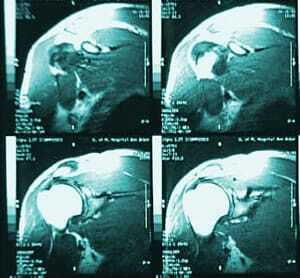

The MRI can be misleading, according to the superstar of superstars, Dr. James Andrews. Dr. Andrews conducted a study in 2011 of 31 professional baseball pitchers. Dr. Andrews found that in 90% of the players, all of them healthy, there was abnormal shoulder cartilage. Dr. Andrews made a point to stress that while the MRI is an invaluable tool in many other situations, it can be overused and inaccurate as well.

While this is a study that was conducted in sports medicine and applies more to people that engage in an active and athletic lifestyle, it does apply to all fields that use the MRI. An MRI is a part, a big part, of helping a patient but it should not be the sole factor in determining how to treat someone. Sports medicine has examples of athletes that have gone unnecessary procedures due to the sole use of the MRI.